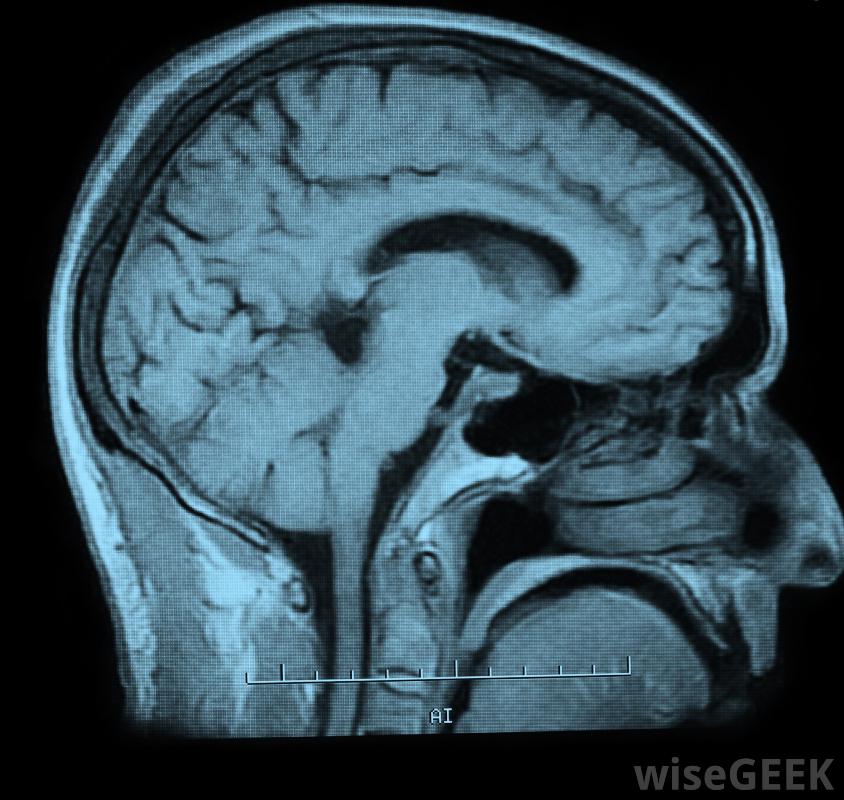

认知科学是一个跨学科的领域,研究认知的机制,或者说大脑和大脑如何工作来获取和操纵知识。它包括对人类大脑、动物大脑和人工智能的研究。因为认知是生命组织和生存机制的基础,认知科学包括一个重要学科的大网络,这个领域的各个分支包括神经科学、生理学、心理学、人类学、语言学、物理学、人工智能或计算机科学以及哲学核磁共振成像使科学家们能够以新的方式描绘大脑。有一句流行的格言是三个蒙着眼睛的人用每个人能感觉到的部分描述一头大象这些描述听起来很相关,但是当眼罩被移开时,双方可以看到他们都在描述同一动物的不同部分。认知科学是一种合作的努力,它认识到每一个不同的学科都揭示了智力的某些方面,从而有助于全面了解大脑是如何通过大脑表现出来的。随着不同学科获得理解,因此,发展认知理论的总体目标最好是由该领域的跨学科性质来实现的src="1234561"/>MRI扫描有助于科学家以新的方式描绘大脑现代成像技术帮助认知科学取得了重大进展。计算机辅助断层扫描(CAT)、正电子发射断层扫描(PET)和磁共振成像(MRI)使科学家能够以新的方式绘制大脑。大脑的特定区域可以与解剖位置相联系,创造一个更好的理解心理和身体的相互关系。尽管人们渴望了解心灵和认知的愿望至少可以追溯到古希腊哲学家,直到人工智能取得进展,认知科学的一个跨学科领域才逐渐发展起来。这个术语是最近由克里斯托弗·朗格特·希金斯(Christopher Longuet Higgins)在1973年提出的。随后1977年,《认知科学》杂志(cognitive science)也在1977年出版,两年后成立了认知科学学会(Society for cognitive science)今天,认知科学是一个激动人心的领域,对全人类都有好处。随着科学家们逐渐了解认知的本质,我们将学习如何更好地运用教学方法,在计算机科学中发展有用的机器人技术,并通过神经科学,更进一步了解大脑。这可能最终导致中风或其他创伤造成的损伤的恢复,或为阿尔茨海默氏症或精神分裂症等疾病提供解决方案。当我们向前迈进时,这一领域的好处似乎很明显可能和认知本身一样支持生命